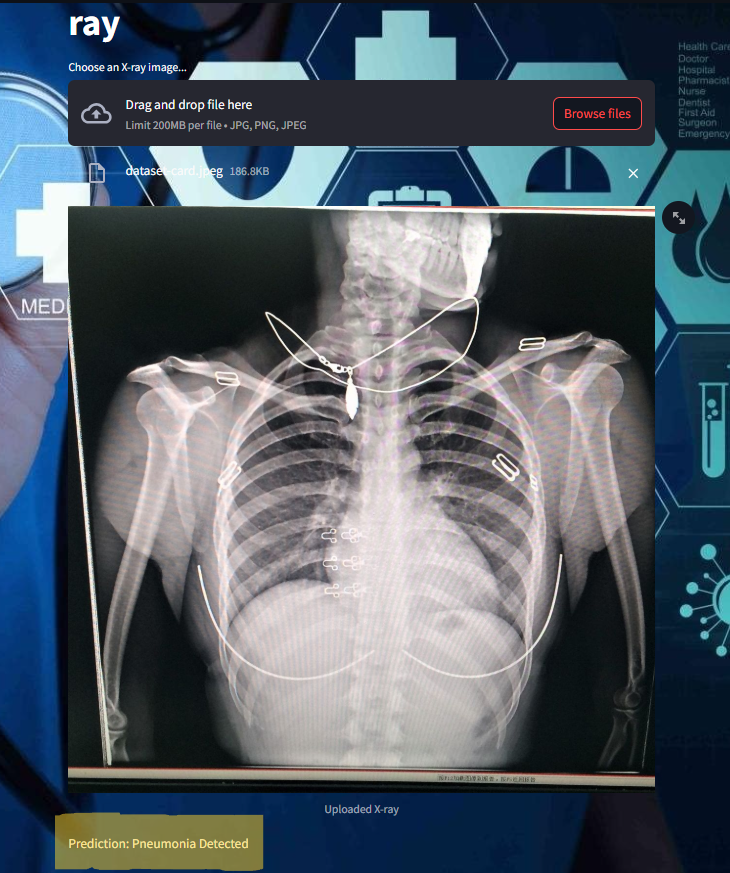

# Import required libraries import streamlit as st from PIL import Image import numpy as np from tensorflow.keras.models import load_model # File upload interface uploaded_file = st.file_uploader("Choose an X-ray image...", type=["jpg", "png", "jpeg"]) if uploaded_file is not None: image = Image.open(uploaded_file) st.image(image, caption='Uploaded X-ray', use_column_width=True) # Convert the image to RGB (if not already in RGB format) image = image.convert("RGB") # Preprocess the image image = image.resize((224, 224)) image = np.array(image) / 255.0 # Normalize the pixel values to [0, 1] image = np.expand_dims(image, axis=0) # Add batch dimension

# Load the trained model model = load_model('pneumonia_model.h5') # Generate prediction prediction = model.predict(image) # Display the prediction if prediction > 0.5: st.write("Prediction: Pneumonia Detected") else: st.write("Prediction: Healthy")

frontend image :

Some of the images of its working,